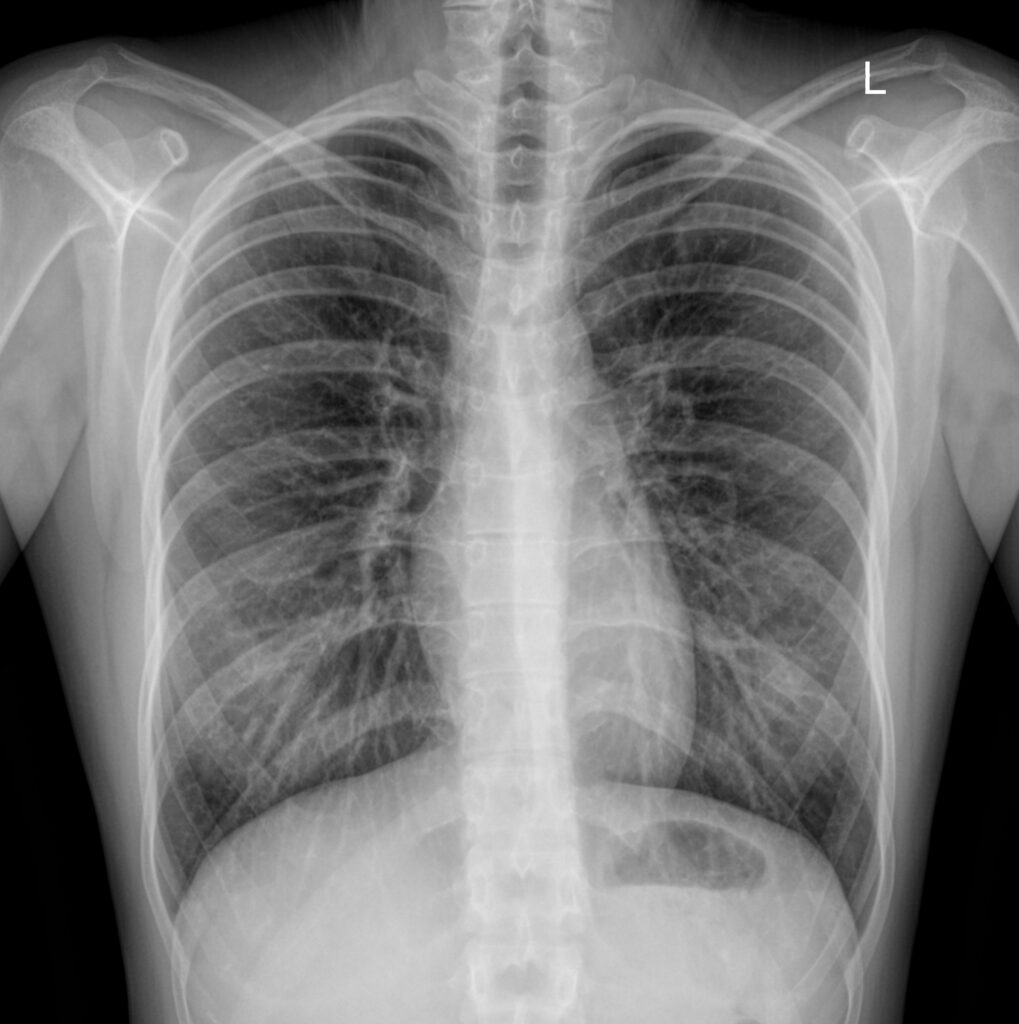

Рентгенография

Такой подход хорошо себя зарекомендовал в клинической практике в качестве быстрого скрининга патологий дыхательной системы и переломов ребер и был введен в перечень обязательных диагностических исследований при поступлении в клинику. При рентгенографии доза облучения крайне мала и никоим образом не сказывается пагубно на состоянии здоровья пациента в настоящем и будущем. Однако, если в качестве обзорного и быстрого исследования данный метод является приемлемым и хорошо себя зарекомендовал, то для выявления мелких патологий данный метод не подходит, так как разрешающая способность рентгена является недостаточной. Но все же в качестве быстрого скрининга такой метод является наиболее оправданным и подходящим, за исключением случаев, когда лечащий врач с большей долей вероятности уверен, что искомая патология будет плохо визуализирована на рентгене. Принципиальные разницы рентгенографии и флюорографии будут изложены в рамках другой статьи.